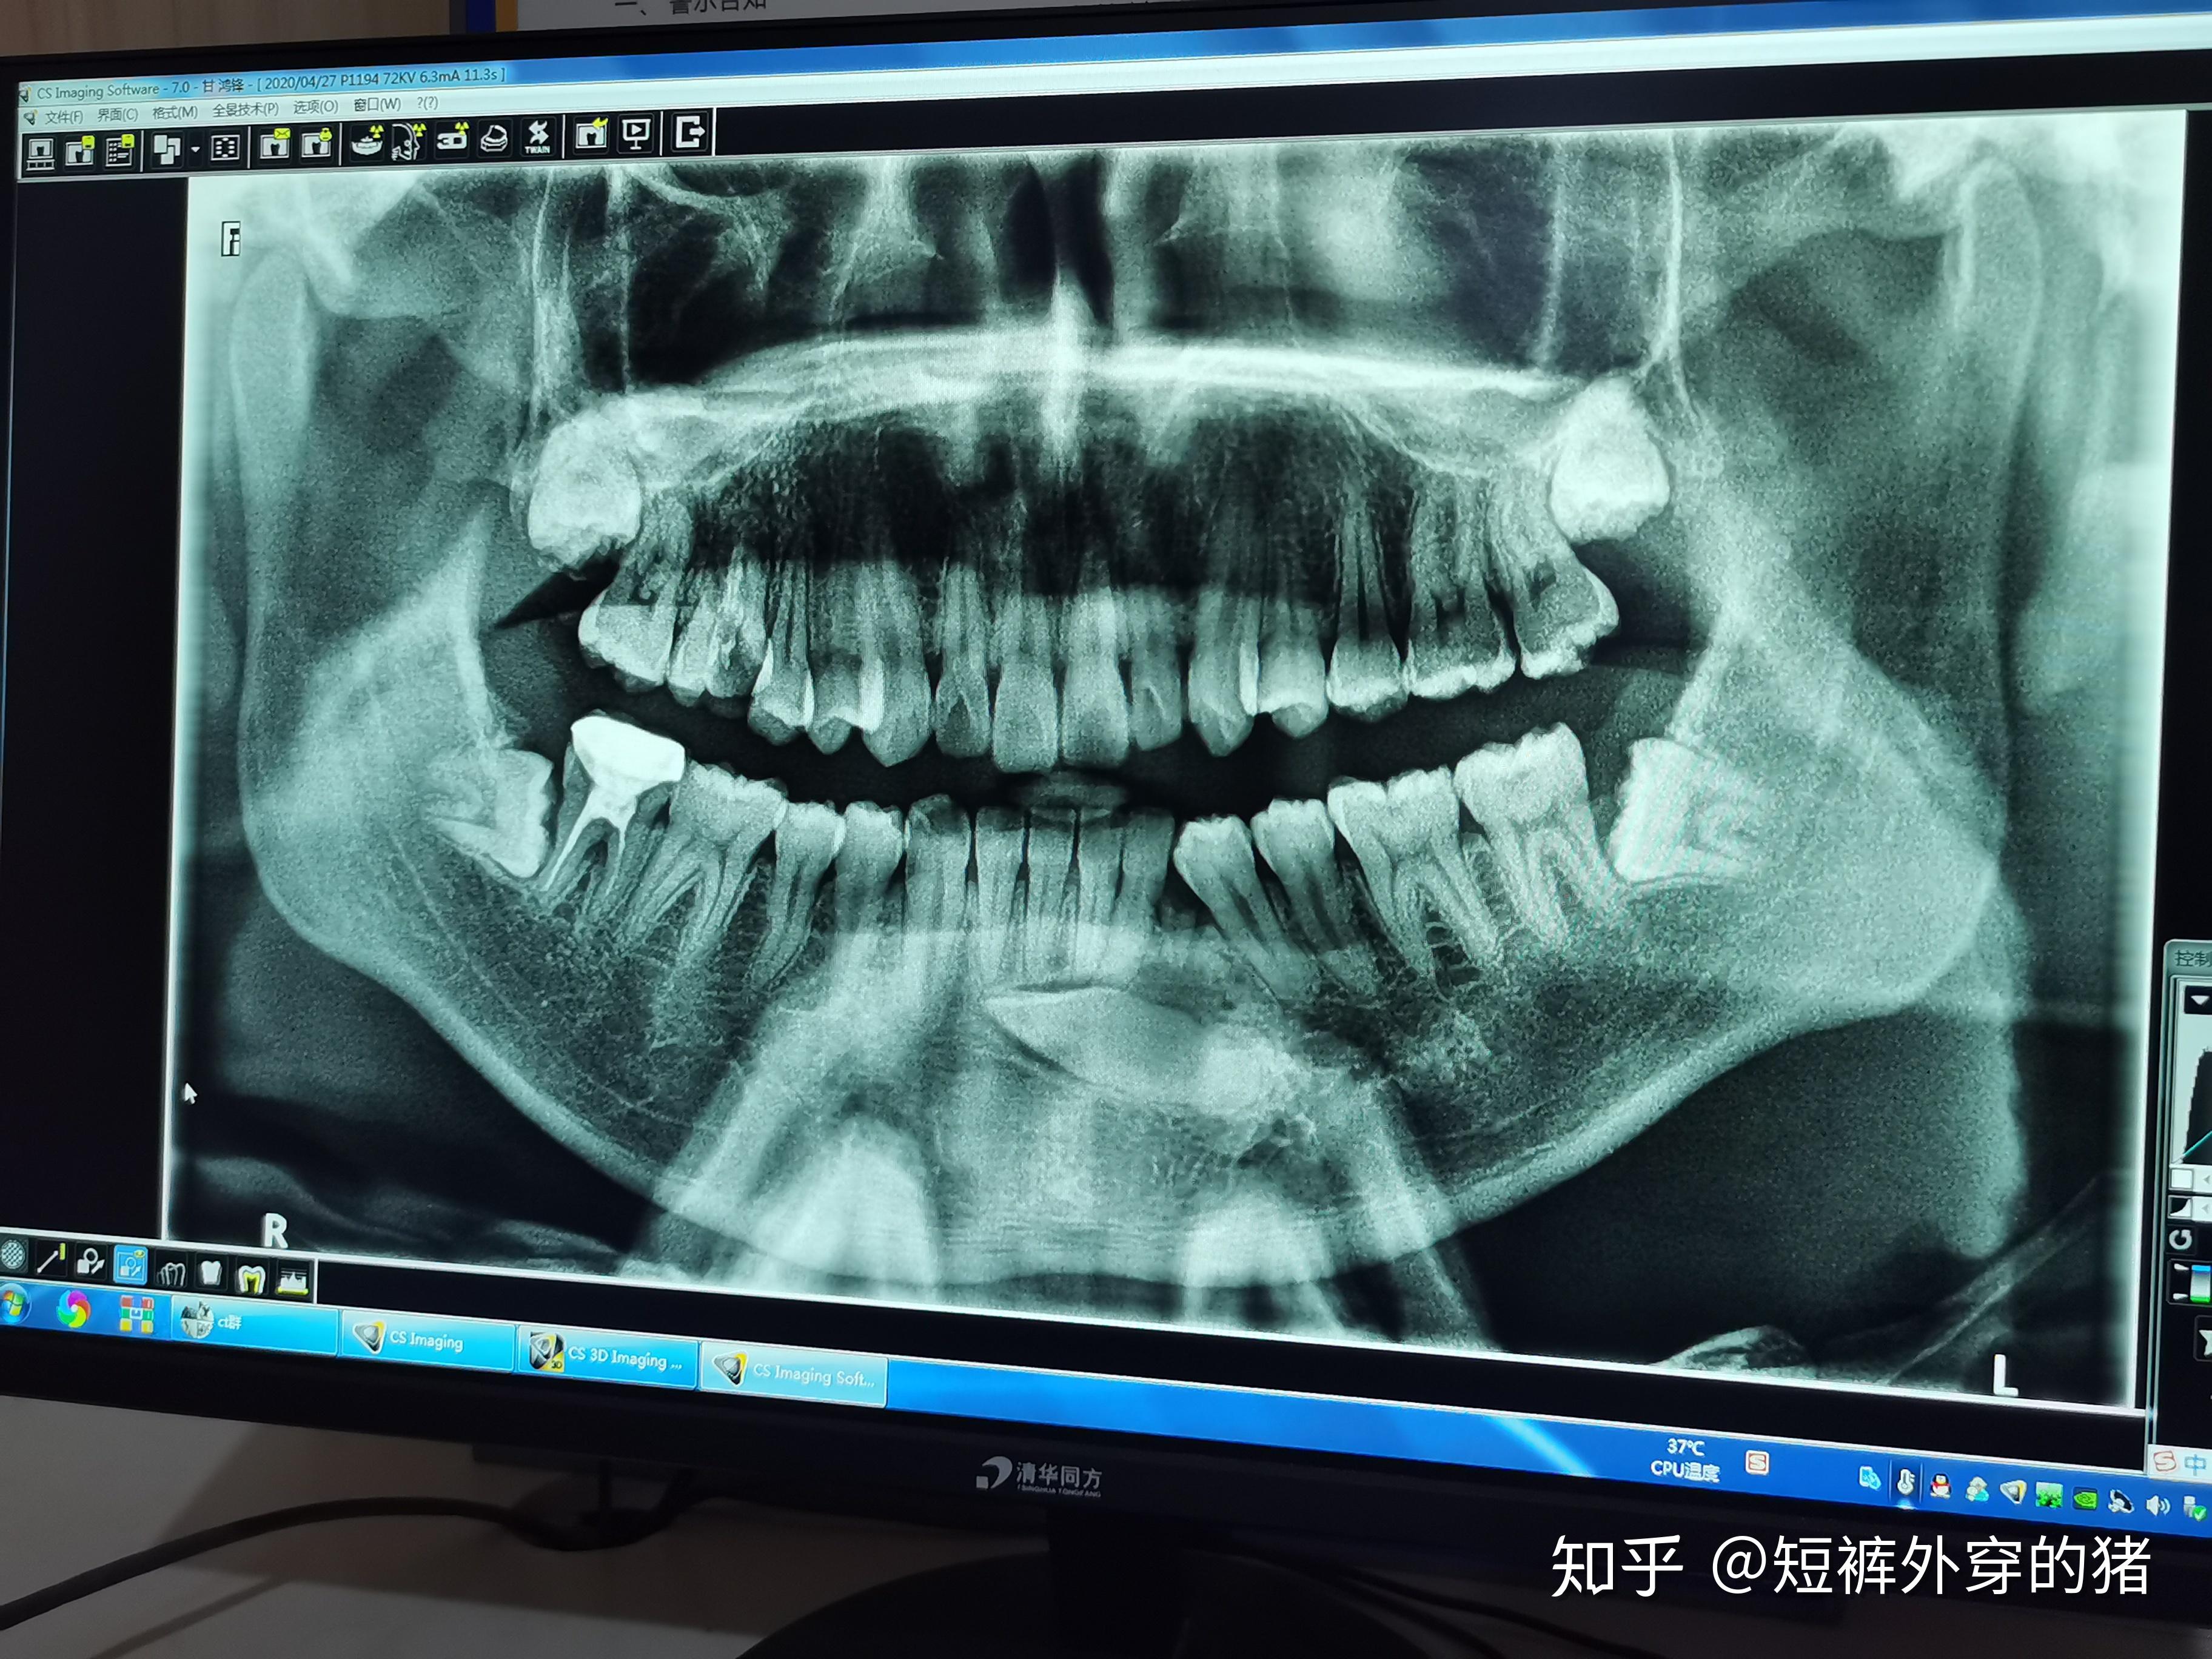

这样的埋伏牙,有必要把掉吗 - 知乎

图片尺寸2560x1444